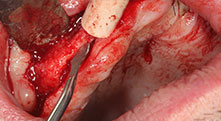

Бихте ли описали накратко, например, Вашия метод за мобилизиране на костни блокове за трансплантация?

Брату: Ние предпочитаме да събираме кост от външната страна на гребена в задната част на долната челюст. След разрязване на меките тъкани, ние използваме новите триони, за да определим количеството кост, което ще събираме. С този подход, ние използваме трионите за цялата препарация в почти 80% от случаите. Може да използваме и други пиезо инструменти и накрая длето за мобилизиране на блока. Ние смятаме, че това е изключително ефективна хирургична техника.